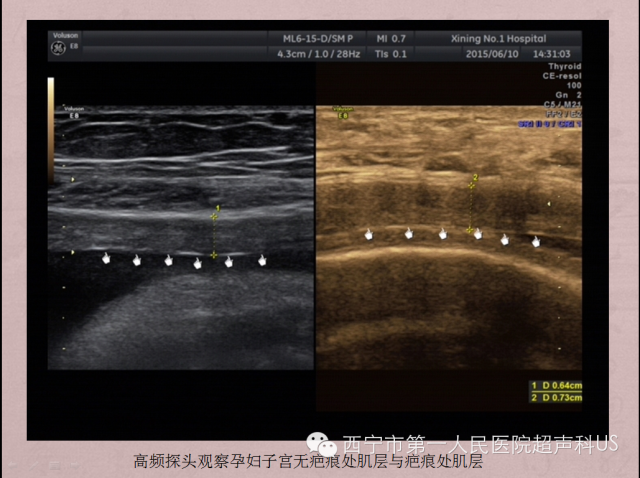

一些作者描述了LUS的测量方法。在超声上,LUS有两层结构,高回声层(包括膀胱壁)和低回声层(代表了子宫肌层)。如果患者膀胱充盈,LUS的界限显示的更清楚。通过纵切和横切,可以找到最薄的区域。为测量LUS的厚度,一个光标置于尿液和膀胱壁之间,另一个光标置于羊水(或胎儿头皮)与蜕膜之间。子宫肌层厚度测量是将第一个光标置于膀胱壁与子宫肌层之间,也就是说只测量低回声层。建议测量三次,取最低值。